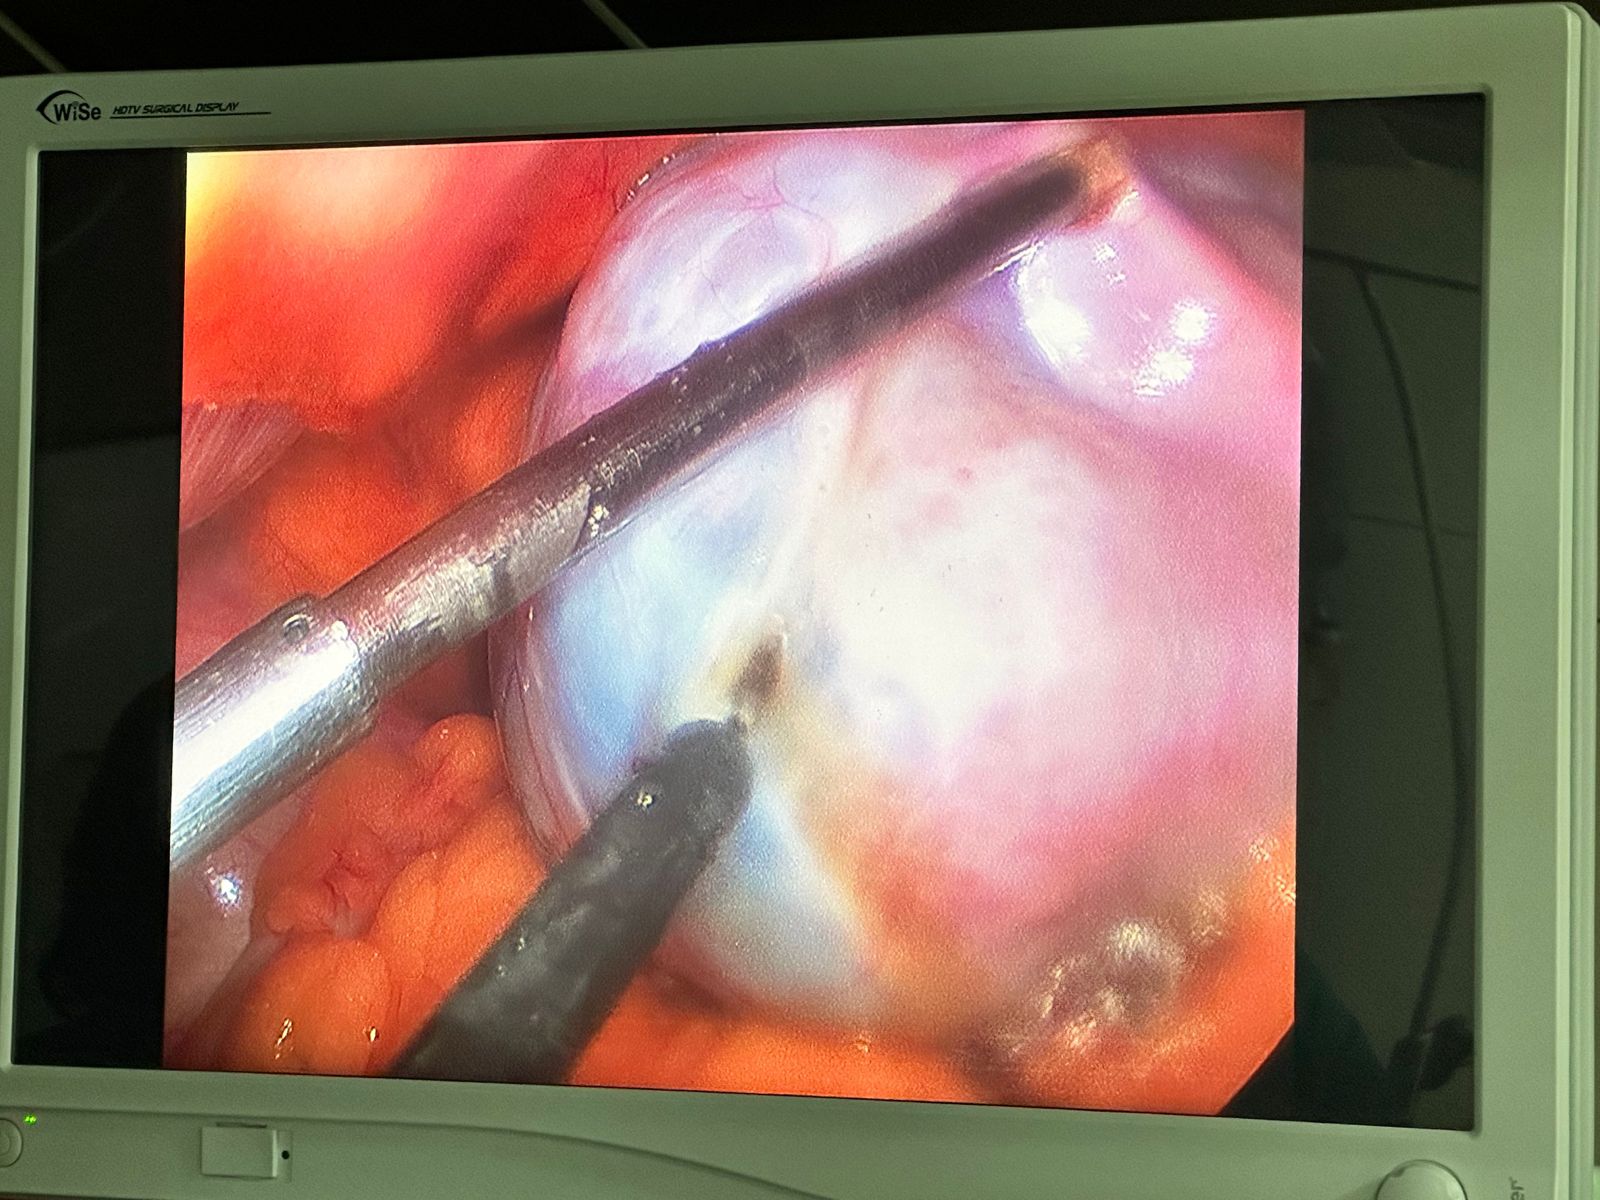

Lap ovarian cystectomy